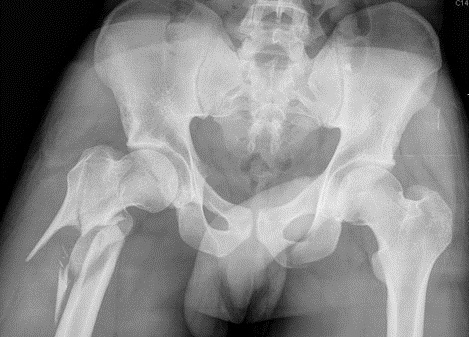

Fig1. - 'Open book' fracture of the pelvis.

Fig1. - Treated with open reduction and internal fixation.